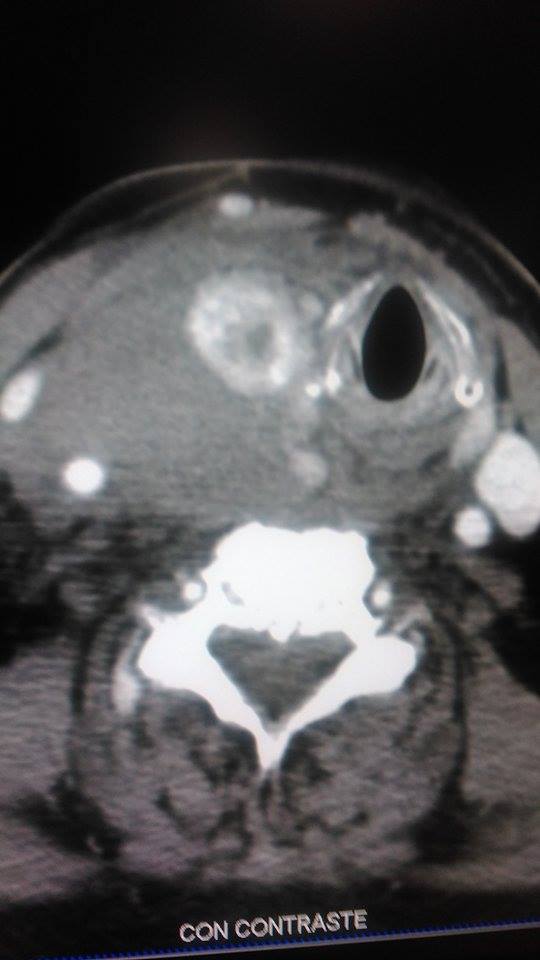

• Tac helicoidal siemens 64 ,donde se realiza protocolo de cuello.

• Se administra contraste Iv dando la imagen que vemos a continuación.

La paciente ha presentado un sangrado activo, con un importante hematoma con desviación de la tráquea totalmente a su izquierda, con compromiso de la vía aérea, compresión de arterias y venas del cuello, hipotensión grave.